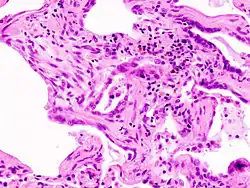

Micrograph of usual interstitial pneumonia (UIP). UIP is the most common pattern of idiopathic interstitial pneumonia (a type of interstitial lung disease) and usually represents idiopathic pulmonary fibrosis. H&E stain. Autopsy specimen.

A lung biopsy may be required if the clinical history and imaging are not clearly suggestive of a specific diagnosis or malignancy cannot otherwise be ruled out. Surgical lung biopsy or via a video-assisted thoracoscopic surgery (VATS) biopsy is associated with a mortality rate up to 1-2%. A bronchoscopic transbronchial cryobiopsy, in which a camera is introduced into the airways followed by rapid freezing of an area of lung tissue prior to biopsy is associated with a lower complication rate and a much lower mortality rate compared to VATS or surgical biopsy with near comparable diagnostic accuracy.[17] There are four types of histopathologic patterns seen in ILD: usual interstitial pneumonia, non-specific interstitial pneumonia, organizing pneumonia, and diffuse alveolar damage.[10] There is significant overlap of the histopathological and radiologic features of each ILD type making diagnosis challenging; even with lung biopsy, 15% of cases of ILD cannot be classified.[10]